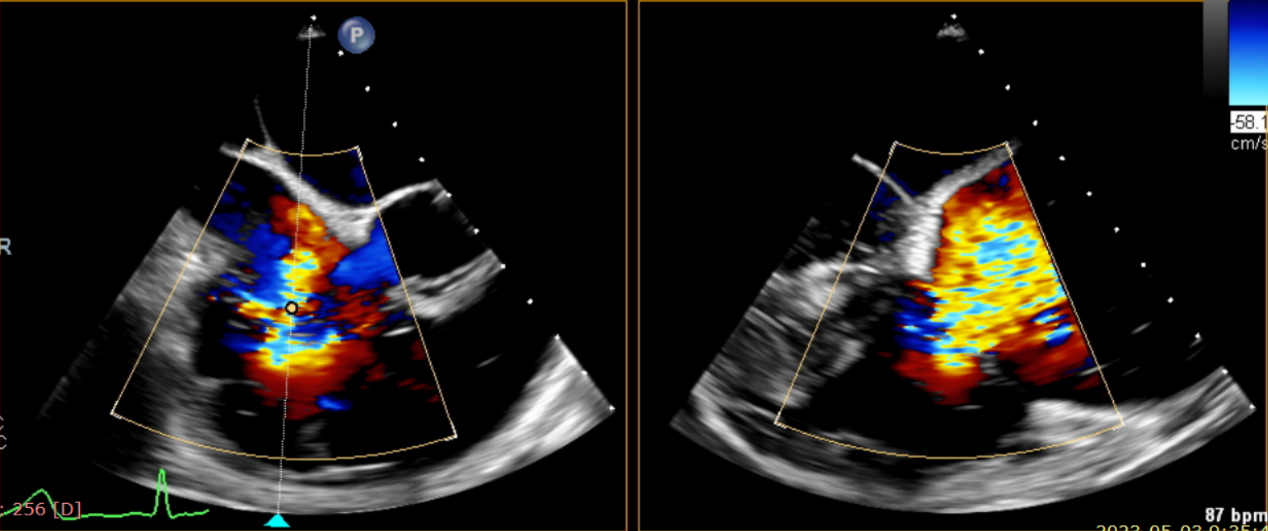

術前超聲提示大量三尖瓣反流

術中輸送器在超聲引導下調整位置

術后超聲提示無瓣周漏

術后超聲提示僅殘余輕微瓣周漏